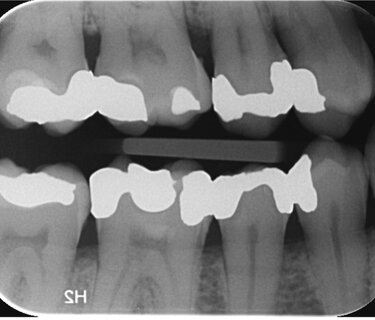

Cracks and fractures associated with amalgam restorations are commonplace in general dental practice. This is especially true if there is a significant loss of tooth structure. Every dentist sees this on a day-to-day basis.

Many of these teeth are structurally compromised, and it is common to find evidence of carious lesions beneath these cracks. Not only that, but it is also common to find carious lesions in the adjacent teeth, mesial or distal to the cracked tooth. Especially if the cracks run interproximally.

This patient presented with a classic representation of the ‘murder house’ days. A quadrant packed full of amalgam fillings, many with surrounding cracks and underlying carious lesions.

The plan was to place four indirect restorations, all done in a single visit. The first premolar and second molar were restored with milled inlays using IPS Tetric CAD. The second premolar and first molar were restored with full coverage restorations using IPS e.max CAD®.